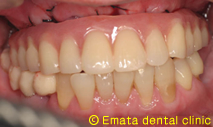

All-on-4(オールオンフォー)とは従来のインプラント治療に大きな変革をもたらす、画期的で最新の治療方法です。たった4本から6本でインプラントで12本分の歯を支えることを可能で手術が終わったとたんに入れ歯から開放され、固定式の歯がはいります。

| All-on-4は4本ではないかとおもいますが、骨の状態や対合歯が自分の歯なのでより確実性をもたせたいため5本で立ち上げ、2本はスリープさせました。

この症例のポイントは、ソケットリフト部位への即時負荷でしょう。アダプテーションテクニックにより40ニュートンの初期固定がえられました(専門的になってしまいましたね)。 麻酔専門医の先生が静脈内鎮静法を行っていますので患者さんは半分寝ているうちに手術が終わってしまいます。 |

仮歯までいれるのに半日かかりましたが、患者様には大変喜んでいただきました。 |